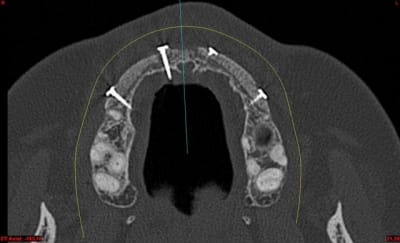

01/05/2011 à 11h48

dentiste57 écrivait:

--------------------

> et là ?

> greffe selon ta méthode ?

Cross section dhvkc8 - Eugenol

3d dt3qom - Eugenol

Overview uqcp6u - Eugenol

S2y2o1v7q53ws4r5wy6ou8czrpom - Eugenol

pxav

01/05/2011 à 12h55

> dentiste57 écrivait:

> --------------------

> > et là ?

> > greffe selon ta méthode ?

expansion, c'est plus cool!